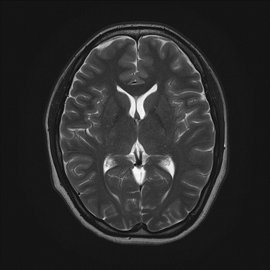

MRIはCTやX線撮影では分からない脳梗塞や、動脈瘤を可視化することができるため、脳卒中患者様においては重要な検査となっています。さらに、神経、靭帯、前立腺胆管、膵管などもよく分かるため、さまざまな診療科で需要は非常に高いです。